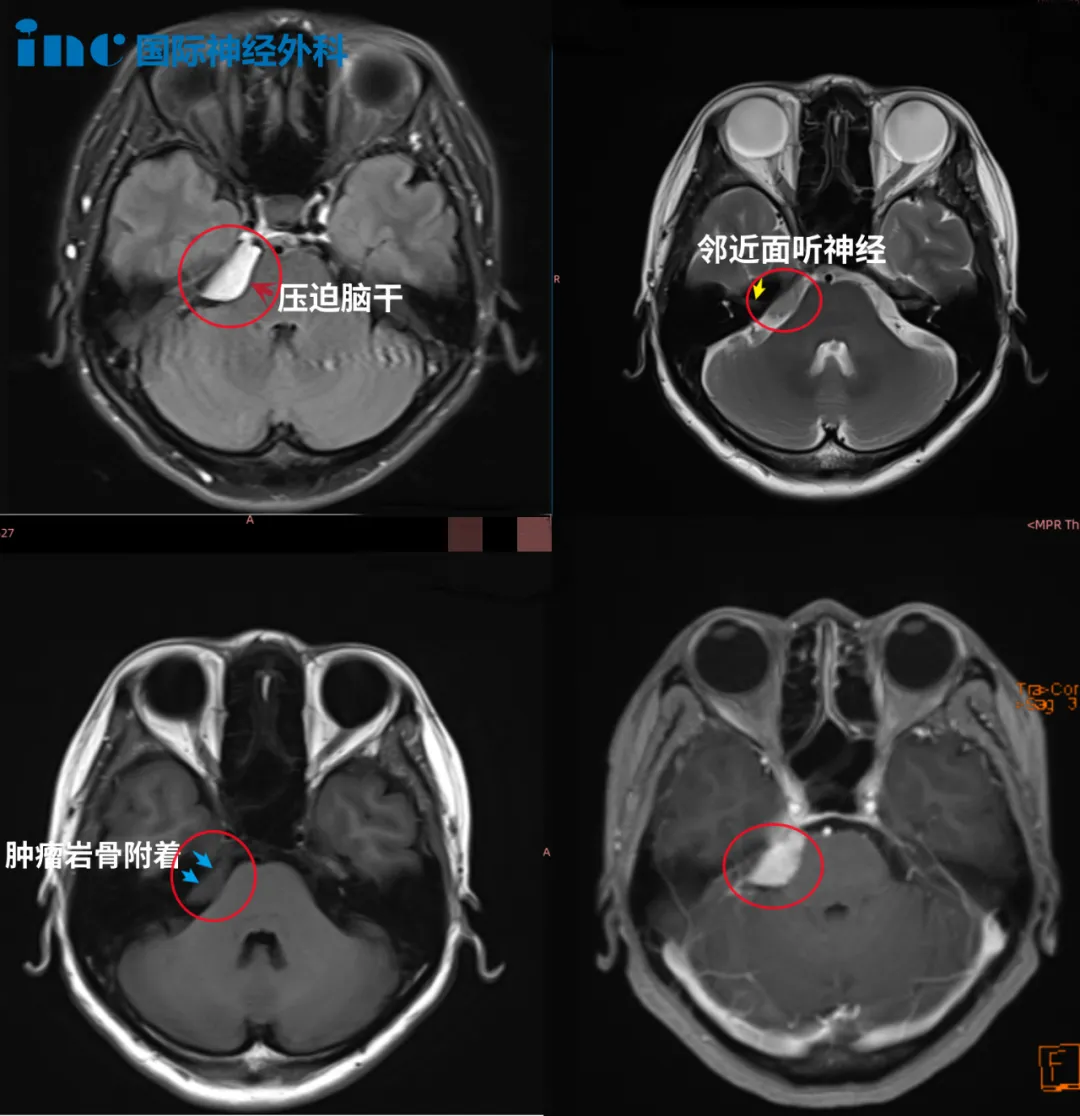

术前情况:2021年9月,50多岁的钟女士在体检中意外查出CPA区脑膜瘤。当时医生告诉她,右侧桥小脑角(CPA)区占位,肿瘤位置附着岩谷、临近面听神经,且已经压迫脑干,手术治疗伤及神经的风险很大,也就是说如果手术做不好,钟女士可能以后开口吃饭、睁眼看东西的力气都没有了,也很可能失去视力和听力。

鉴于手术风险很大,钟女士在医生的建议下选择了伽马刀治疗,并且她找了国内伽马刀医院进行治疗,可是七八个月过去了,并没有明显治疗效果,这使她更焦虑了。

钟女士在INC医学顾问的协助下与巴教授展开了远程咨询,巴教授建议手术治疗,显微外科手术可以很好地完成肿瘤切除,不会出现并发症。谨慎的评估肿瘤切除率在97到99%之间,巴教授评估患者术后面瘫发生率为3%,而实际很多患者手术后没有并发症出现。巴教授还提到如果是初治时,根据肿瘤的位置,大小和患者的年龄等因素,他会建议患者手术,而不是伽马刀治疗。因为如果选择放疗,仅能减瘤、无法根治肿瘤。而且放疗会导致肿瘤和神经焦灼黏连、手术分离切除肿瘤难度更大,放疗后手术效果降低。

手术情况:2022年巴教授中国行中,成功主刀手术肿瘤全切,无新发神经功能损伤。术后一天ICU查房,钟女士状态清醒,和教授交流顺畅。术后五天查房,钟女士状态良好,连声感谢巴教授并和教授开心合影。病理结果脑膜瘤WHOI级,良性预后很好,术后将不再需要反复放化疗,她可以像正常人一样生活。

▼术前术后MRI对比